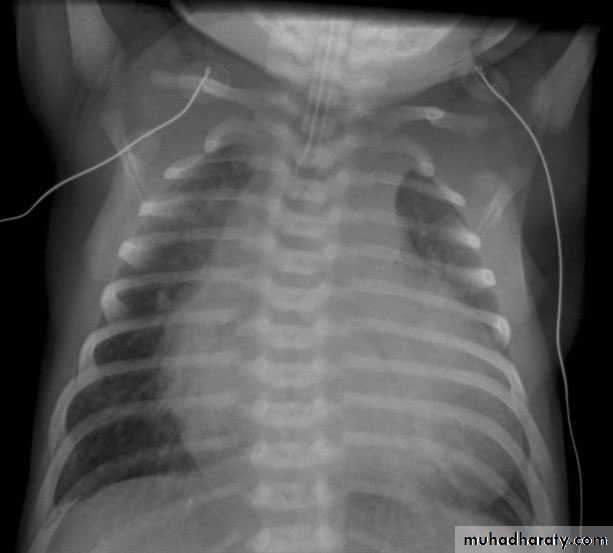

CXR will show increased pulmonary vascular markings. The ‘snowman’ sign (enlarged superior mediastinum) is seen in supracardiac TAPVR to the left innominate vein in older infants.

CXR : Egg on side & narrow mediastinum